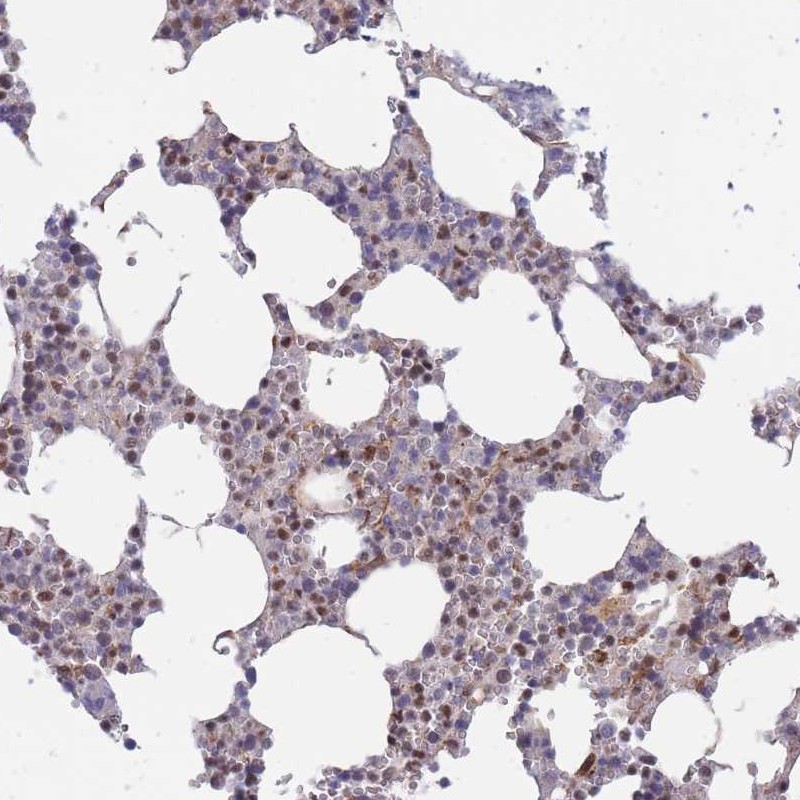

Immunohistochemical staining of human bone marrow shows nuclear positivity in hematopoietic cells.